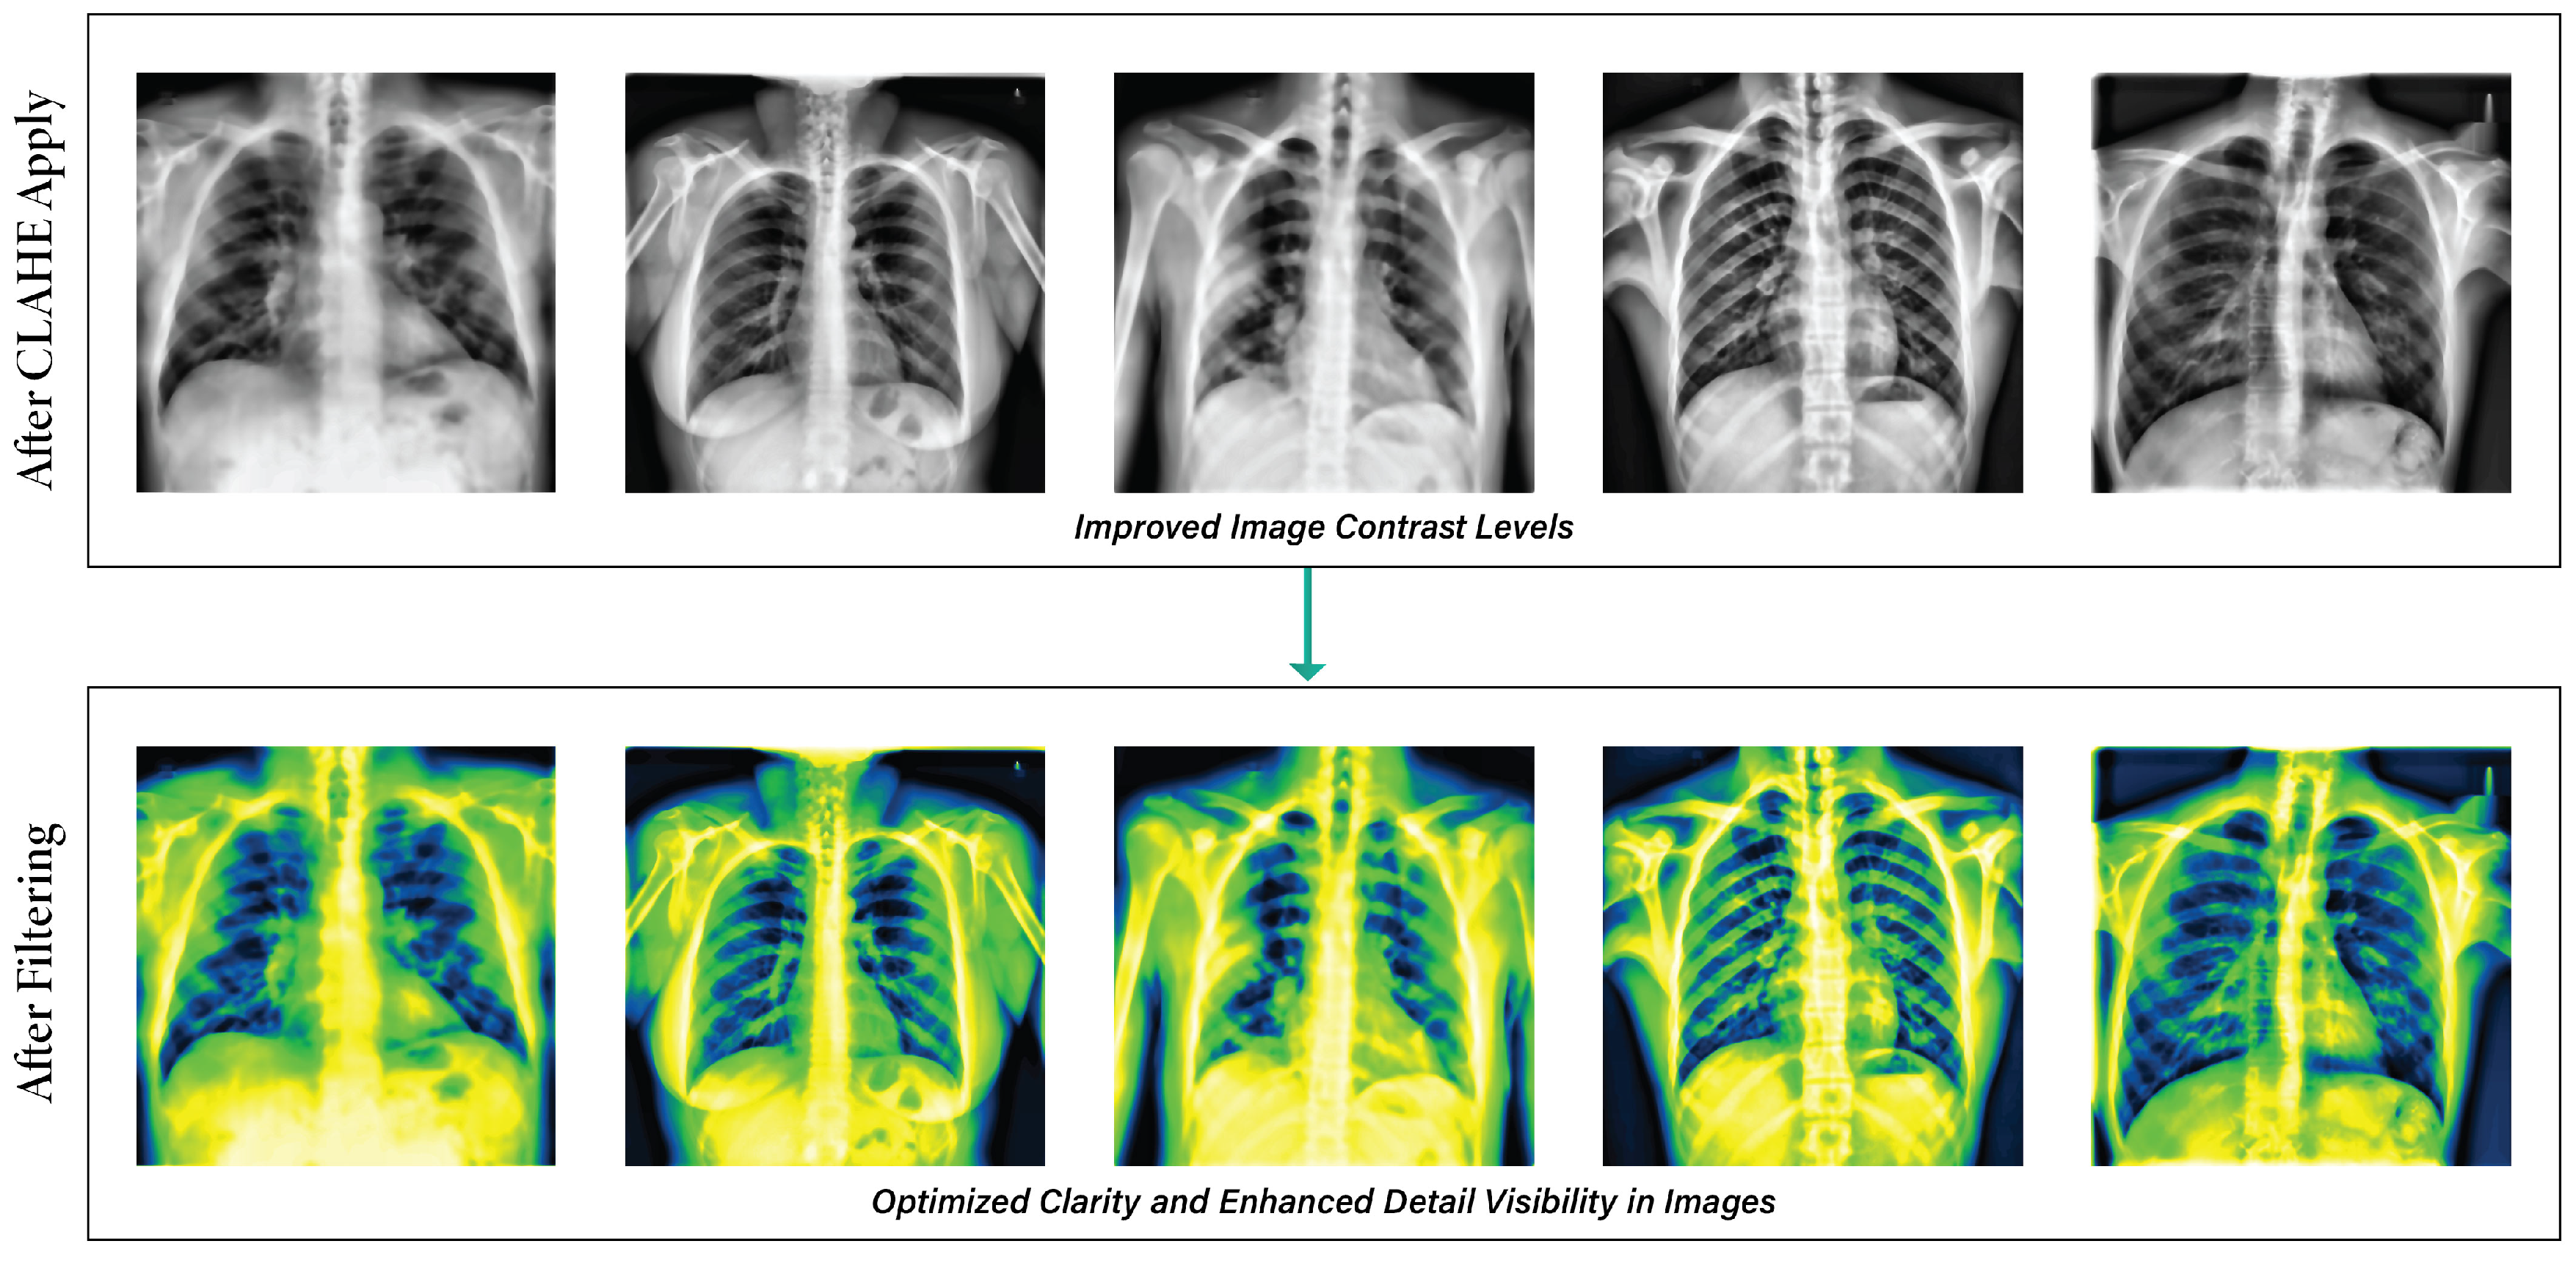

3.2.5. Filter Application

- Effective image pre-processing techniques improve lung disease classification accuracy by reducing noise and artifacts. In this regard, we resized all images to the same pixel. The de-annotation method improves images by removing annotations and extraneous text, and the enhancement method enhances image properties. We used elastic deformation methods to add random distortions to the data to balance the distribution of underrepresented class images.